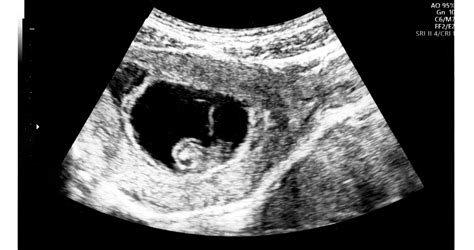

A hCG szintje a terhesség korai szakaszában rohamosan nő, a maximumát a 10-12. terhességi hét körül éri el. A különböző érzékenységű terhességi gyorstesztek a vizeletben kimutatható hCG emelkedett szintjére reagálnak.